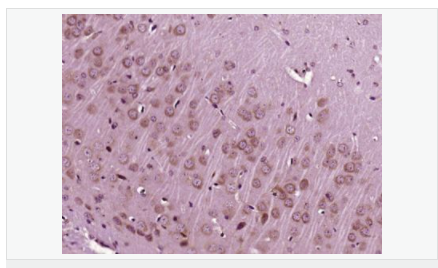

| 產(chǎn)品應(yīng)用 | WB=1:500-2000 ELISA=1:5000-10000 IP=1:20-100 IHC-P=1:100-500 IHC-F=1:100-500 IF=1:100-500 (石蠟切片需做抗原修復(fù)) not yet tested in other applications. optimal dilutions/concentrations should be determined by the end user. |

| 產(chǎn)品介紹 | The protein encoded by this gene is similar to insulin in function and structure and is a member of a family of proteins involved in mediating growth and development. The encoded protein is processed from a precursor, bound by a specific receptor, and secreted. Defects in this gene are a cause of insulin-like growth factor I deficiency. Several transcript variants encoding different isoforms have been found for this gene.[provided by RefSeq, Mar 2009] Function: The insulin-like growth factors, isolated from plasma, are structurally and functionally related to insulin but have a much higher growth-promoting activity. May be a physiological regulator of [1-14C]-2-deoxy-D-glucose (2DG) transport and glycogen synthesis in osteoblasts. Stimulates glucose transport in rat bone-derived osteoblastic (PyMS) cells and is effective at much lower concentrations than insulin, not only regarding glycogen and DNA synthesis but also with regard to enhancing glucose uptake. Subcellular Location: Secreted. DISEASE: Defects in IGF1 are the cause of insulin-like growth factor I deficiency (IGF1 deficiency) [MIM:608747]. IGF1 deficiency is an autosomal recessive disorder characterized by growth retardation, sensorineural deafness and mental retardation. Similarity: Belongs to the insulin family. SWISS: P05019 Gene ID: 3479 Database links: Entrez Gene: 3479 Human Omim: 147440 Human SwissProt: P05019 Human Unigene: 160562 Human Important Note: This product as supplied is intended for research use only, not for use in human, therapeutic or diagnostic applications. 胰島素樣生長(zhǎng)因子1(IGF-1)是一種生長(zhǎng)調(diào)節(jié)激素,由肝分泌并入血液循環(huán)的中性多肽,具有調(diào)節(jié)生長(zhǎng)和代謝、胰島素樣及促細(xì)胞分裂的活性,主要作用于成人。 |